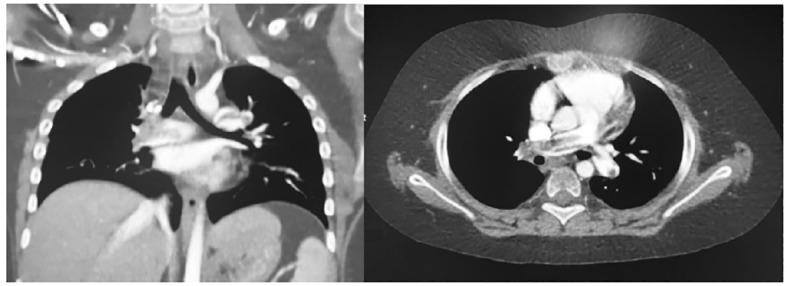

Five patients (26.3%) presented vascular events, which all occurred in connection with sodium imbalances. Three DVT (two with associated pulmonary embolism, in one case leading to death) developed in the post-operative period, most frequently at 7-10 days. Elevated D-dimers, a reduced partial activated thrombin time and a prolonged C-reactive protein increase were highly related to thrombotic vascular events. One case of posterior cerebral artery pseudoaneurysm was described soon after neurosurgery, requiring vascular stenting. Superficial vein thrombophlebitis was a late complication in one patient with other predisposing factors.

5 名患者(26.3%)出现血管事件,这些事件均与钠失衡有关。3 例 DVT(其中 2 例合并肺栓塞,1 例导致死亡)发生在术后,最常发生在术后 7-10 天。升高的 D-二聚体、部分激活的凝血酶时间缩短和 C 反应蛋白升高延长与血栓性血管事件高度相关。1 例术后不久即出现大脑后动脉假性动脉瘤,需要血管支架置入。1 例有其他诱发因素的患者出现浅表静脉血栓性静脉炎的晚期并发症。